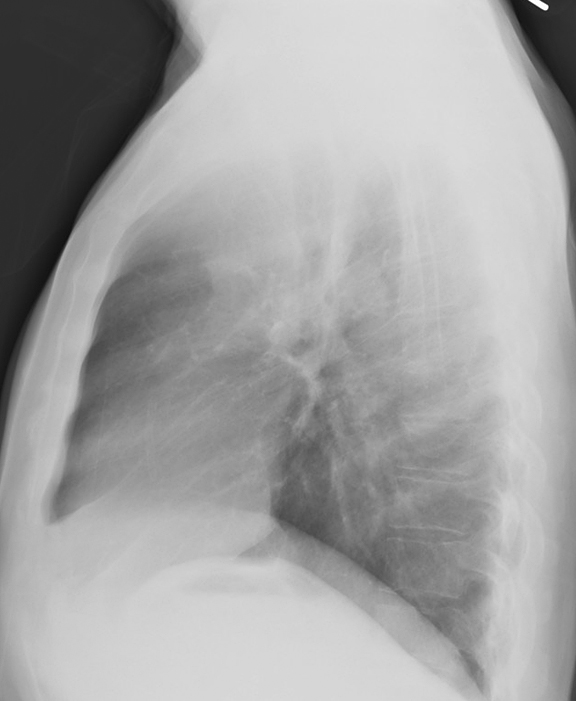

RUL Collapse Case 4 Lateral